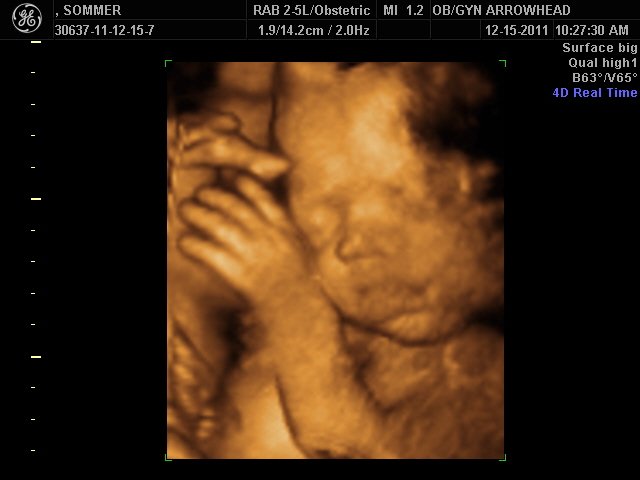

We offer complimentary 3D/4D Ultrasounds to all our OB patients around 30 weeks! The following photos are some examples of our work, shown with permission from our patients.